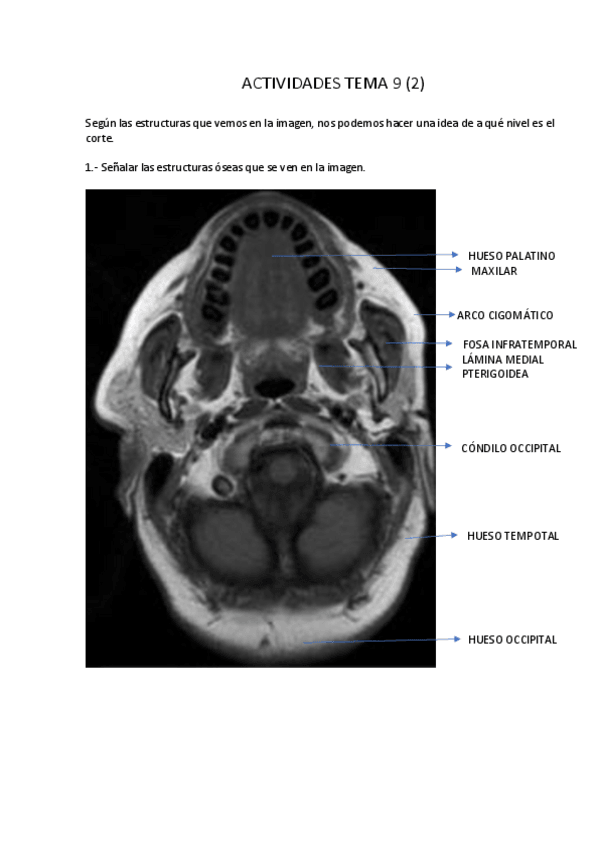

Apuntes - Tema-9-Cavidad-craneal.pdf

Apuntes - Tema-9.pdf